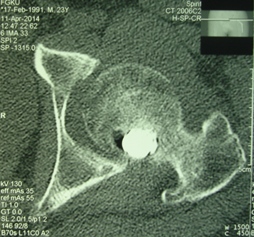

Уважаемые коллеги, приношу извинения за перерыв в работе -

был в командировке. За это время больному сделали КТ и,  сегодня,

снимки. Укорочение конечности - 1-1,5 см, ШДУ-115 градусов, замедленная консолидация,

остеопороз.

Вопрос о тактике дальнейшего ведения пациента (напоминаю, возраст 19

лет)?